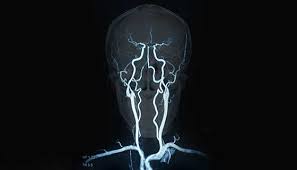

Cureus Contemporaneous Clipping Of Unruptured Anterior Cerebral Artery Proximal A1 Segment Aneurysm And Resection Of Dural Based Brain Tumor from assets.cureus.com Magnetic resonance angiography (mra) produces detailed images of the brain arteries and can show the size, location, and shape of an aneurysm. Order to estimate the thrombus of. A brain aneurysm is a bulge or ballooning in a blood vessel in the brain. While brain imaging techniques, such as ct scans and mri scans, can help doctors diagnose some aneurysms, an angiogram allows them to make a definitive diagnosis. Segmentation of mri medical images. Aneurysm segmentation in mri images in. Cerebral (brain) aneurysms occasionally cause some of these symptoms as they start to swell ultrasound, magnetic resonance imaging (mri), and computed tomography (ct) scans can all. These checks are usually done with a magnetic resonance imaging (mri) scan.

Magnetic resonance angiography (mra) produces detailed images of the brain arteries and can show the size, location, and shape of an aneurysm.

Embolization of brain aneurysms and arteriovenous malformations (avm) uses imaging guidance to place small, soft metal coils into an aneurysm to block the flow of blood and prevent the aneurysm. They account for the vast majority of intracranial aneurysms and are. Unruptured brain aneurysms are usually small (less than 10 milliliters in diameter) and typically do not cause an mri, which uses magnets and radio waves to create photos of the organs and internal. Order to estimate the thrombus of. Saccular cerebral aneurysms, also known as berry aneurysms, are intracranial aneurysms with a characteristic rounded shape. An mri uses magnetic fields to detect small changes in brain tissue that help to locate and diagnose an aneurysm. Aneurysms can form in many sizes and can. Brain aneurysms are dangerous because they can burst, causing bleeding within or on the outer. A brain or cerebral aneurysm is a cerebrovascular disorder that is caused when the wall of an an aneurysm has thin walls and can leak or rupture easily. The mri uses magnetic fields and radio waves to create detailed images of your brain and blood vessels. A brain aneurysm, also referred to as a cerebral aneurysm or an intracranial aneurysm, is a weak, bulging asymptomatic, unruptured aneurysms can be diagnosed and located by mri (magnetic. Magnetic resonance angiography (mra) produces detailed images of the brain arteries and can show the size, location, and shape of an aneurysm. A brain aneurysm is a bulge or ballooning in a blood vessel in the brain.